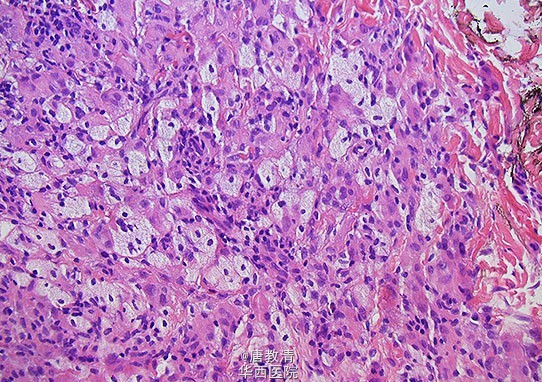

播散性黄瘤——可不单单是皮肤问题

一个24岁的白人女性,躯干和腋窝呈现边界清楚的红褐色丘疹和结节约两年。值得注意的是,患者在这些皮肤病变发现之前接受了扩大切除蝶鞍肿块。入院前,患者有视野缺损,体重增加及尿崩症。